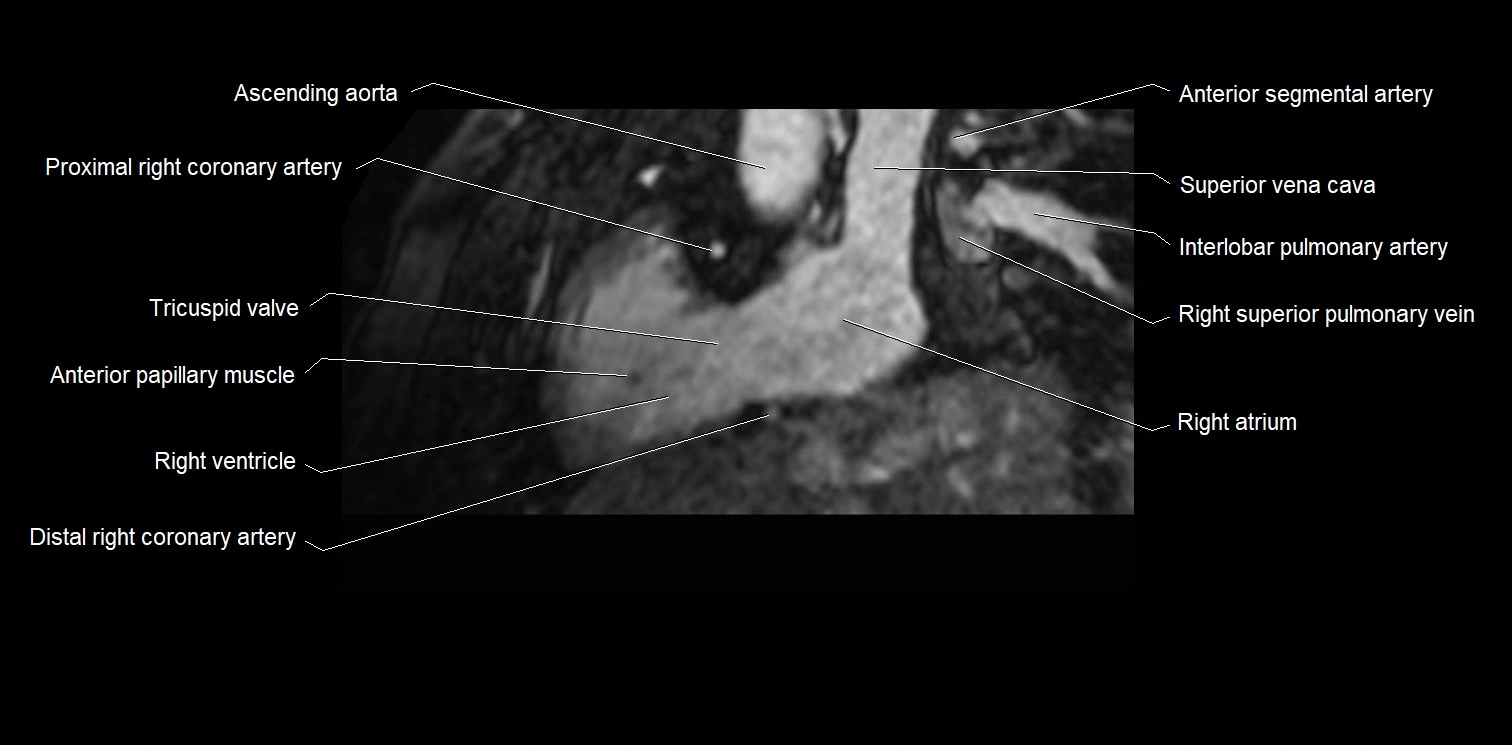

- Ascending aorta

- Right coronary artery (RCA)

- Right atrioventricular valve (tricuspid valve)

- Anterior papillary muscle

- Right ventricle

- Right atrium

- Right superior pulmonary vein

- Right posterior descending coronary artery (Right PDA)